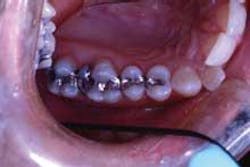

A 30-year-old female presents all four quadrants of her posterior teeth with amalgam restorations in varying degrees of functionality (Figure 1).

Tooth No. 2 has a large amalgam and the distal-lingual cusps test positive for a fracture. Tooth No. 3 has two large amalgams and recurrent decay. Tooth No. 4 has some marginal breakdown and has recurrent decay distally. Tooth No. 5 has some minor marginal breakdown.

The patient is presented a treatment plan to restore this quadrant of teeth. As each of her other posterior quadrants show similar restorative dentistry, a treatment plan is created quadrant-by-quadrant. Each quadrant is prioritized in the development of the treatment plan.